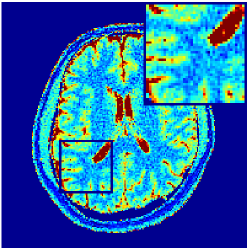

Two sets of experiments were conducted here: first, we used the 2D and 3D acquisition sequences for scanning a healthy volunteer’s brain (real-world acquisitions). Figures 6 and 7 display the parametric maps reconstructed from 2D spiral and radial readouts. We computed the T1, T2 and proton density (PD) maps using baseline reconstruction algorithms ZF, VS, LR, FLOR, AIR-MRF and our proposed LRTV. While baselines use DM either for quantitative inference or also during reconstruction (i.e. AIR-MRF), we further compare the DM-free LRTV’s performance when cascaded to DM, KM and MRFResnet for quantitative inference. For the 3D spiral acquisitions we compared LRTV and its closest competitor VS in Figure 8. Outcomes from other tested algorithm are displayed in the supplementary materials (Figure S5). Since FLOR does not use dimensionality-reduction, our system ran out of memory during 3D reconstruction; hence results are not reported in this case.

VI-E1 Discussion

The LRTV-DM and LRTV-MRFResnet perform on par, and both outperform all tested baselines for reconstructing T1, T2 and PD maps in all acquisition schemes. This can be observed both visually in Figures 6, 7, 8, S2 and S3, and quantitatively in Table IV across all tested metrics. Other baselines were unable to successfully remove the under-sampling artefacts in TSMIs, and these errors propagated to the parameter inference phase and resulted in inaccurate maps. Temporal-only priors incorporated within LR are shown insufficient to regularise the inverse problem and LR sometimes (e.g. 2D spiral acquisitions) can admit solutions with even stronger artefacts than the model-free ZF baseline. This issue was previously studied for other non-Cartesian MRF readouts that similar to our spiral/radial trajectories, miss to sample the corners of the k-space in all timeframes (see section 2.2.2 and figure 2 in [19]). In the absence of reference for the k-space corners information, the LR iterations despite minimising the objective can converge to solutions with high-frequency artefacts, as visible in the computed maps. This highlights the need for adding an appropriate spatial-domain regularisation. FLOR reduces the LR’s artefacts but this improvement is limited because the suggested nuclear norm penalty does not incorporate an explicit spatial regularisation. Further for reducing artefacts, FLOR can introduce an undesirable bias in the computed T1/T2 maps e.g. see error maps in Figures S2 and S3. The non model-based VS baseline incorporates spatial regularisation and results in spatially smoother maps than ZF and LR, but it is unable to output artefact-free images. Further and consistent with our in-vitro experiment, we observe that VS overestimates the T2 values (e.g. in White and Grey matter regions) in tested 2D acquisitions i.e. the spatial regularisation trades off agains the quantification accuracy. The model-based AIR-MRF adds spatial regularisation through 2D/3D low-pass Gaussian filters however this trades off the sharpness of the computed maps and can increase the errors at the tissue boundaries (we searched Gaussian spreads that keep the blurs and high-frequency artefacts minimal). For our acquisition readouts, Gaussian filters performed better than disk filters of [19] for avoiding strong Gibbs artefacts. On the other hand, the spatiotemporally regularised LRTV greatly improves the TSMI reconstructions i.e. 4 dB enhancement compared to the closest competitor baseline (Table IV). This enables computing accurate and aliased-free multi-parametric inference using DM or the DM-free learning-based alternative MRFResnet as visible in Figures 6, 7, 8, S2 and S3. MRResnet and DM score competitive quantitative inference results i.e. T1 and T2 MAPE less than 5% and 9%, respectively (Table IV). KM also outputs comparably accurate T1 maps, however this shallow learning model despite having a model size larger than MRFResnet, is unable to learn accurate T2/PD quantification and it results in poor estimated maps, consistent with our observations in section VI-C.